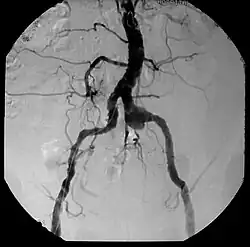

Aneurysm, a commonly lethal complication of SA

Syphilitic aortitis is inflammation of the aorta associated with the tertiary stage of syphilis infection. SA begins as inflammation of the outermost layer of the blood vessel, including the blood vessels that supply the aorta itself with blood, the vasa vasorum.[3] As SA worsens, the vasa vasorum undergo hyperplastic thickening of their walls thereby restricting blood flow and causing ischemia of the outer two-thirds of the aortic wall. Starved for oxygen and nutrients, elastic fibers become patchy and smooth muscle cells die. If the disease progresses, syphilitic aortitis leads to an aortic aneurysm. Overall, tertiary syphilis is a rare cause of aortic aneurysms.[3] Syphilitic aortitis has become rare in the developed world with the advent of penicillin treatments after World War II.

Inflammatory involvement of tertiary syphilis begins at the adventitia of the aortic arch which progressively causes obliterative endarteritis of the vasa vasorum.[3] This leads to narrowing of the lumen of the vasa vasorum, causing ischemic injury of the medial aortic arch and then finally loss of elastic support and dilation of the vessel.[3] Dissection of the aortic arch is rare due to medial scarring. As a result of this advanced disease process, normal methods of angiography/angioplasty may be impossible for those with suspected coronary artery disease.